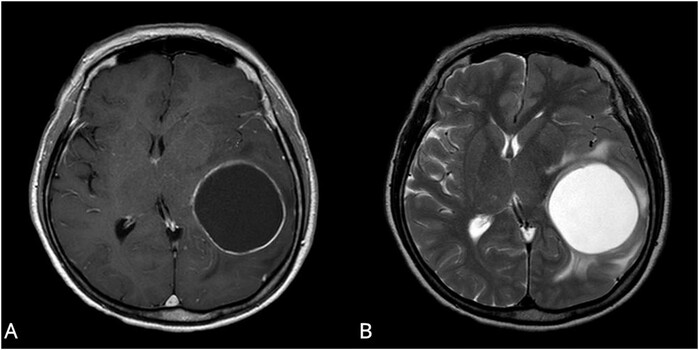

| ▲낭종 이 있는 낭성군(A)환자가 비낭성군(B) 환자에 비해 유의하게 생존기간이 길었다[사진=서울성모병원] |

가톨릭대학교 서울성모병원 신경외과 안스데반 교수(교신저자, 제1저자: 김민주 가톨릭 의과대학 학생)팀이 MRI 검사에서 관찰된 낭의 유무에 따라, 낭성군 및 비낭성군으로 분류하여 어느 군이 더 좋은 예후를 보이는지 알아보고자, 2008년 8월부터 2020년 12월까지 서울성모병원에서 교모세포종을 진단받은 모든 환자들의 기록을 후향적으로 검토하였다. 254명의 교모세포종 환자 중에서, 최종적으로 총 145명이 선정기준을 충족하였으며, 16명은 낭성군으로, 129명은 비낭성군으로 분류됐다

성향 점수 매칭 (propensity score matching) 통계를 활용해 두 군의 다른 예후인자와 연관된 인자를 동일하게 맞춘 후, 카플란-마이어 생존 곡선을 분석한 결과, 낭성군의 생존기간이 28.6개월로 비낭성군의 18.8개월 보다 유의하게 길었다. 다변량 분석에서도 낭이 종양에서 차지하는 비율이 높을수록 환자의 생존기간이 유의하게 길었다.